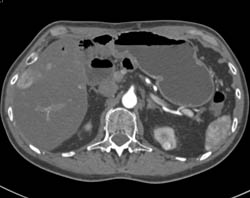

Multiple Renal Arteries